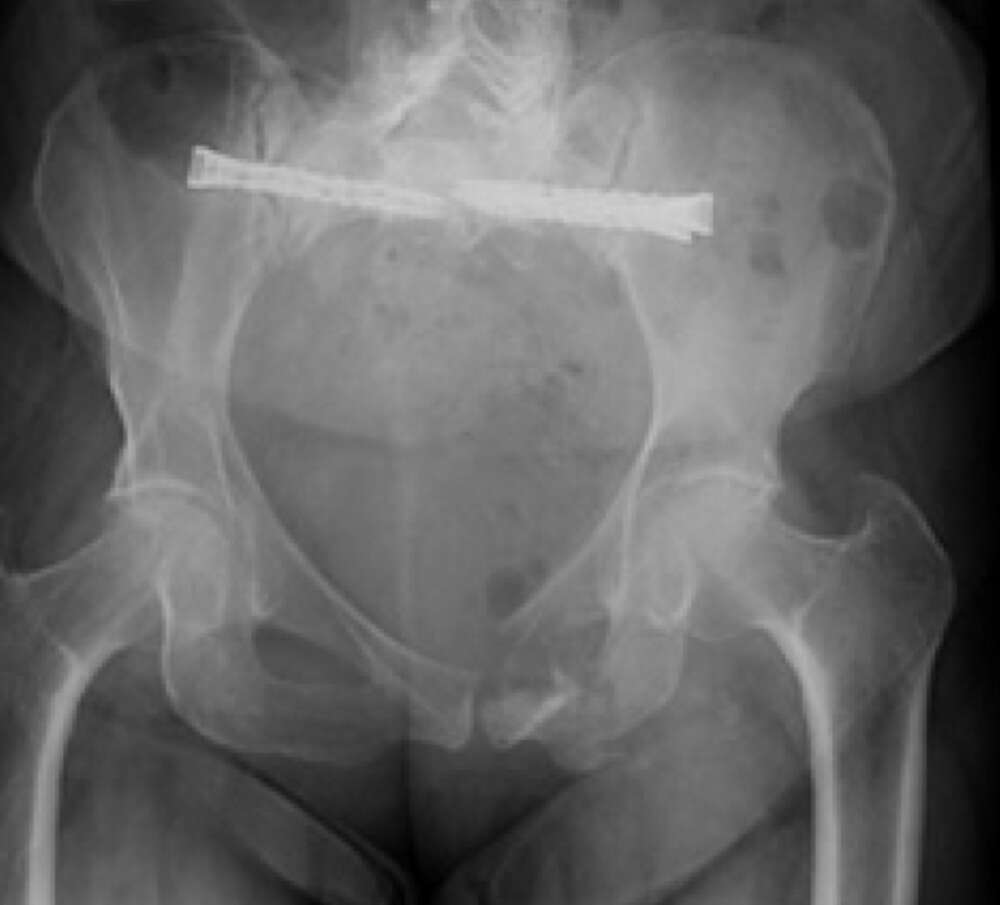

Diagnosis:

• Chronic Sacral U-type fracture with kyphotic deformity

• Anterior ring disruption

• Osteopenia

Surgical treatment:

• Bilateral sacral fracture fixation with iFuse TORQ®